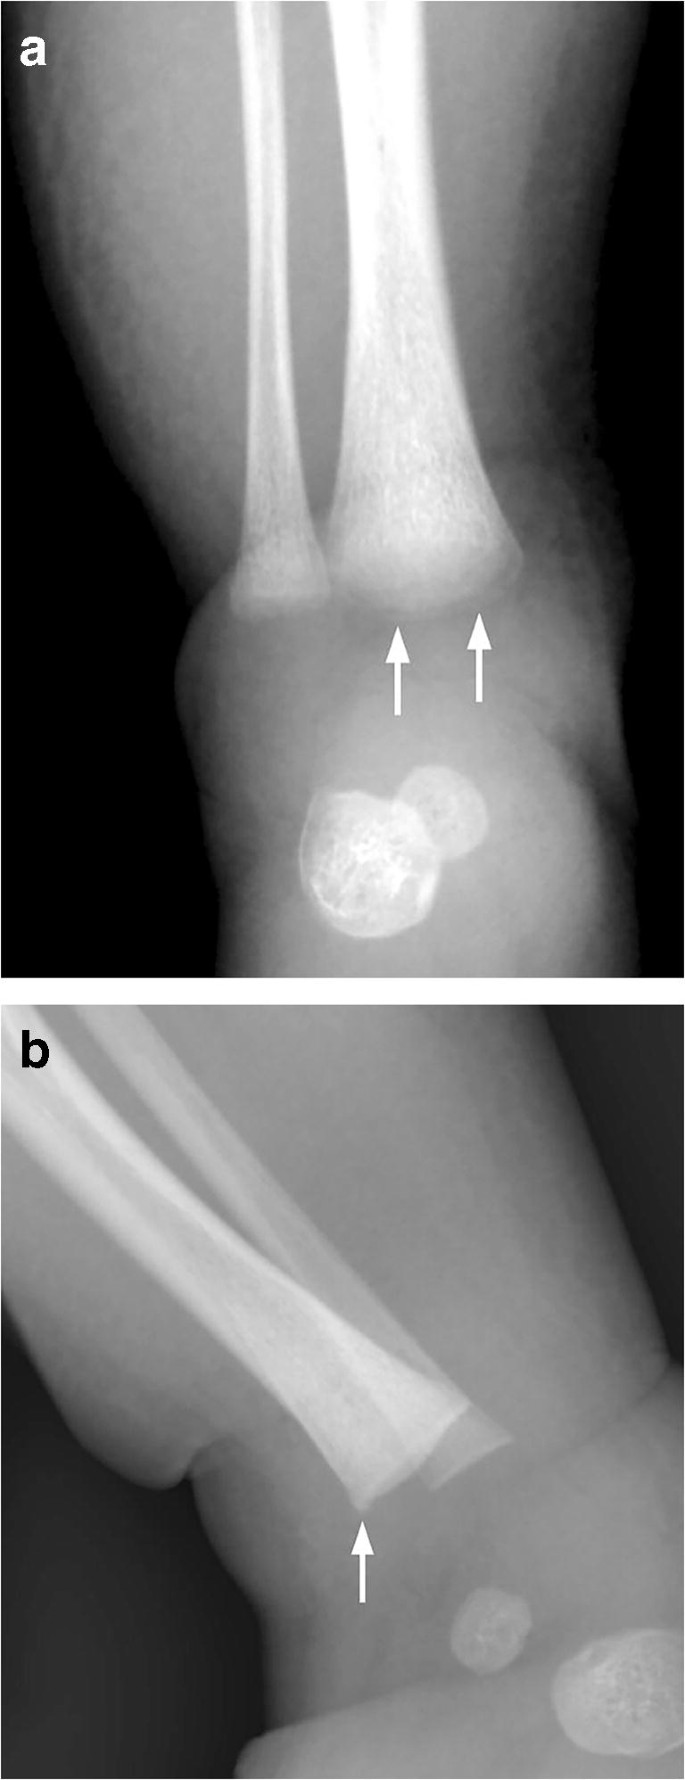

radiological dating of fractures and even less relating fractureagetochildabuse . Themostcomprehensivereview is byO'ConnorandCohen .' . . . Fresh fractures , including metaphyseal fractures , have sharply defined margins . With the development of an osteoclastic response to necrotic bone the fracture ends

These metaphyseal abnormalities were identified from postmortem radiogra-phy and correlated with microscopy . The au-thors concluded the metaphyseal alterations represented partial or complete planar micro- fractures that transected the primary spongio-sa adjacent to the growth plate . These micro- fractures usually resembled a "bucket-handle"

Specific fractures . A number of fractures have been recognised as highly specific to non-accidental injuries (rather than accidental injury) . They include: metaphyseal fracture (so-called bucket handle fracture or corner fracture ) present in up to 39-50% of abused infants <18 months; said to be virtually pathognomonic of NAI; rib fractures